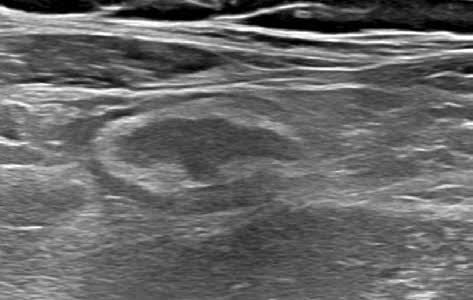

Obr. 4–7: Elastografie. U pacienta s Crohnovou nemocí ve fázi aktivního zánětu vidíme edematózní stěnu s prosáknutím a uzlinami v okolí (5). Elastograficky je stěna „měkčí“ (4) ve srovnání s pacientem s chronickou fází onemocnění (6, 7), u kterého je stěna fibrózně změněná.